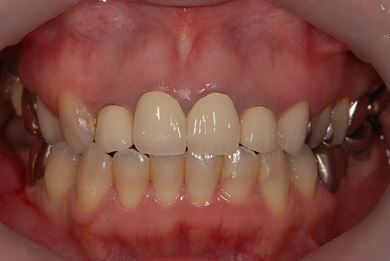

インプラントの症例写真 IMPLANT

インプラント治療

| 性別/年齢 | 女性 / 34歳 | ||||||||||||||||||||||||||||||||

| 主訴 | 左上奥の歯茎の腫れと、口臭などが気になっています。 | ||||||||||||||||||||||||||||||||

| 治療方針 | 右下奥欠損部分をインプラント治療にて機能的・審美的回復を行う。 | ||||||||||||||||||||||||||||||||

| 治療内容 | インプラント1本、メタルボンドセラミッククラウン1本 | ||||||||||||||||||||||||||||||||

| 総治療費 | 252,000円 | ||||||||||||||||||||||||||||||||

| 治療期間 | 4ヶ月 |